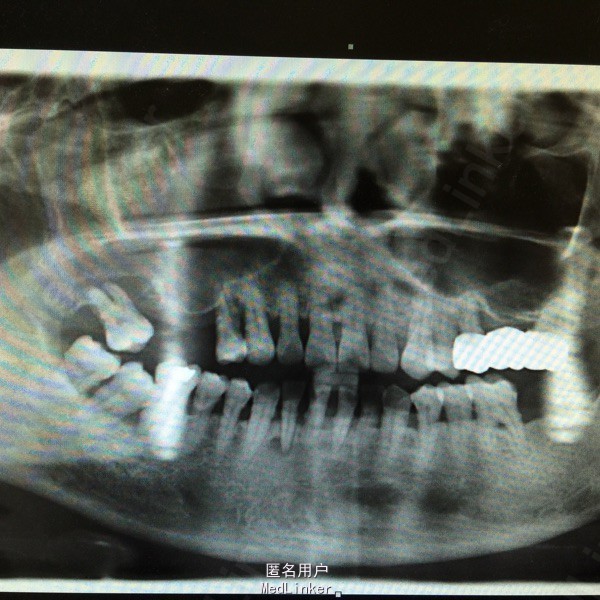

检查:17未及明显龋及隐裂,叩诊(-),松动III度,牙龈无明显红肿,萎缩至根中下1/3,牙周袋约3mm,冷(-)。 全景片示:17根尖位于上颌窦内,右侧上颌窦密度增高。

诊断:17牙周炎 上颌窦慢性炎? 治疗:17局麻下拔除,常规拔牙术后医嘱。 择期行上颌窦根治术及口腔上颌窦瘘修补术。

讨论:有时松动明显的牙周炎拔除没有难度,容易忽视术前片的拍摄,结果导致病人口腔上颌窦瘘,要引起重视,以免发生不必要的纠纷。 此病例为学生拔牙没有认真读片,上颌窦病变没有诊断出来,同时也没有意识到口腔上颌窦瘘的发生。